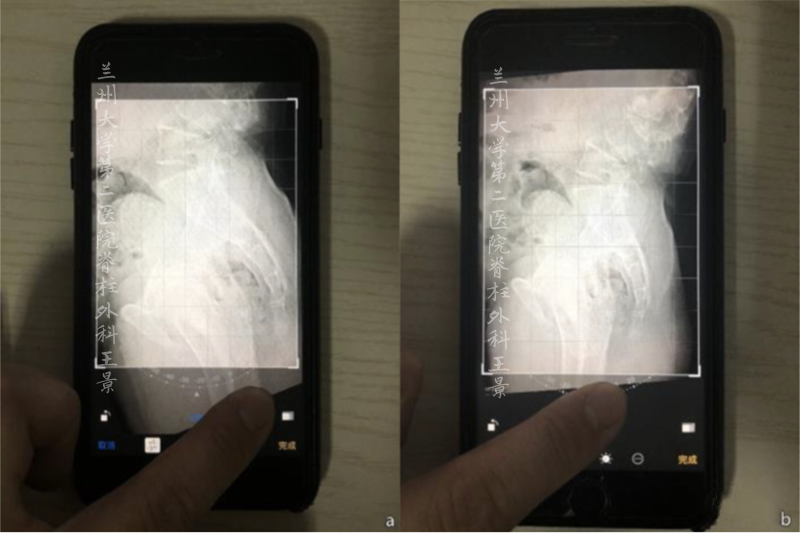

打开照片,进入编辑模式

手指按着屏幕旋转照片

iOS自带的功能

图片旋转时会显示网格线及旋转角度

顺时针/逆时针旋转分别显示±°

精度为1°

如图所示旋转照片

S1上终板与水平线重叠/平行

旋转角度就是骶骨倾斜角

即SS=32°

再重新旋转图片

让股骨头中垂线与网格垂线重叠

旋转角度就是PT(-8°)

如果方法掌握熟练

或者为了大概估算

那么提前做的标记线可以省略

利用目测大概估计

从而达到快速测量目的